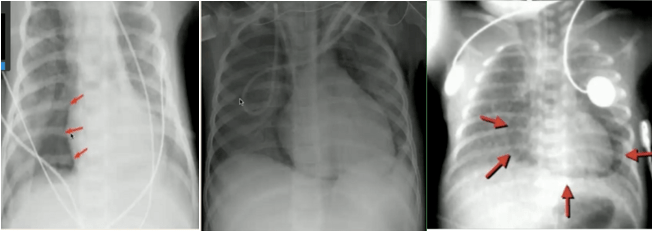

如何阅读儿童胸片(上)-钟礼立

儿童胸片 儿童胸片有点复杂,千万不要随便下诊断,一定要会识别儿童

如何阅读儿童胸片(下)-钟礼立

读完此文,终于会看儿童胸片了

儿童肺炎胸片图解

小儿肺炎胸片图片